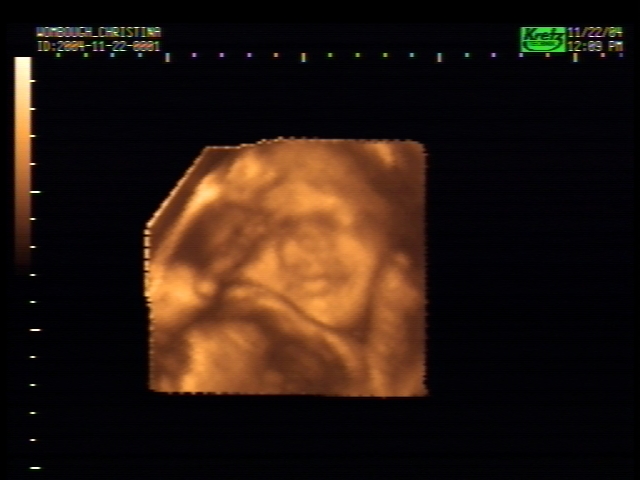

3D Sonogram Pictures